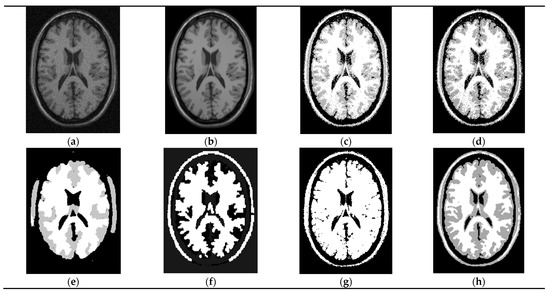

4.5. Segmentation of a Medical Image